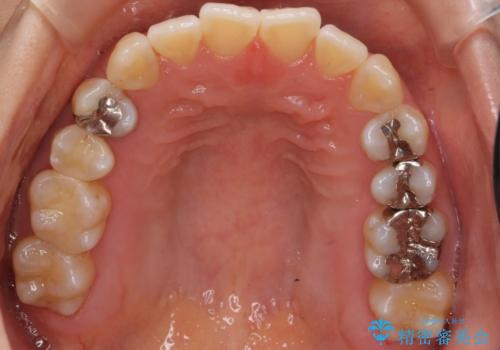

前歯のがたつき 若干受け口 インビザラインで

治療症例の内容

- 前歯のねじれおよび下の前歯が前に出ていることを気にして来院。

インビザラインで治療をおこないました。

前歯のねじれもなおり、比較的短期間でご満足いただけました。

部分矯正コースでしたので左下67の段差は特に治しておりません。

右下567及び左下6の虫歯治療も一緒に行っています。